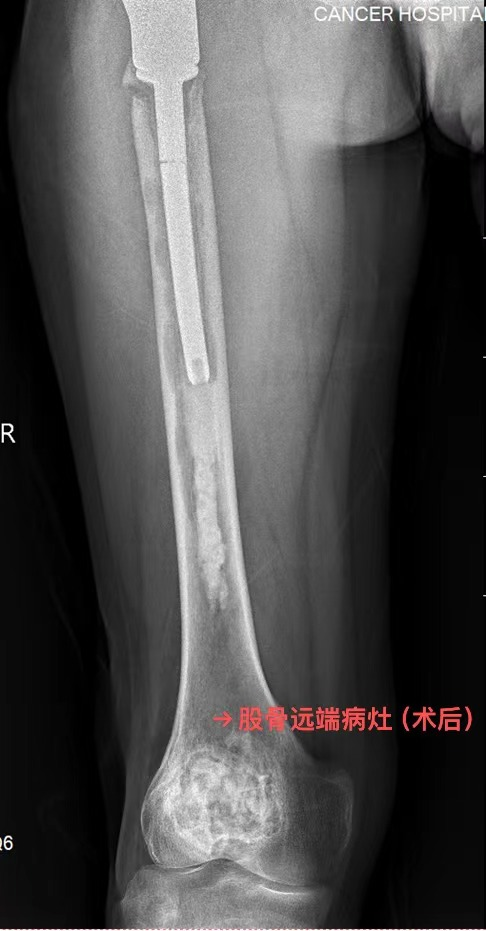

然而命运多舛,半年前他因为假体松动在外院进行了右人工股骨头翻修术,仅仅过了几个月,他再次感觉行走不稳,完善检查后发现再次出现假体松动并且假体柄断裂。转诊多家医院后,此次他决定到我院骨科门诊就诊。

图片 1.png图片 2.png

术前影像

▶ 本例患者骨巨细胞瘤累及股骨颈、股骨远端、胫骨近端等多个部位,属骨巨细胞瘤中的罕见类型。